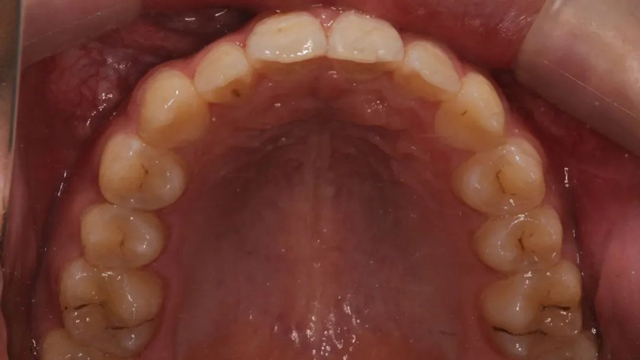

該病例的治療周期長(zhǎng)達(dá)三年,跨替牙期和年輕恒牙期。治療結(jié)束時(shí),小患者收獲了一口整齊美觀的牙齒,也從滿臉稚氣的孩童長(zhǎng)成了青蔥少年。

“這位小朋友的拔牙和開(kāi)窗手術(shù)都位于前牙區(qū),對(duì)美觀的要求更高,最終的矯正效果非常自然。”

2024年9月(矯正結(jié)束后口內(nèi)照)

“隱形矯正一般2-3月復(fù)診一次,從節(jié)約時(shí)間來(lái)說(shuō)很受家長(zhǎng)青睞,但前提是小朋友要有很好的依從性,這是獲得滿意效果的前提。案例中的這個(gè)小朋友和家長(zhǎng)與醫(yī)生的配合度非常高,這也是我們能治療成功的必要因素。”